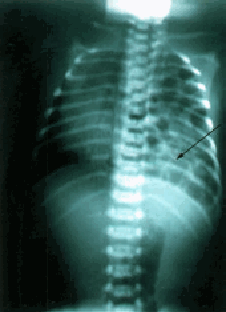

Un neonato masculino a término de 3 300 g nació por cesárea debido a desproporción fetopélvica, situación transversa persistente y ruptura prematura de membranas. El embarazo fue controlado y complicado con polihidramnios. A las tres horas de vida, el neonato presenta dificultad respiratoria con retracción torácica. Los sonidos respiratorios eran simétricos y la puntuación de Silverman de 2 a 3. Se diagnosticó pulmón asfíctico y se indicó oxígeno por cámara al 40 %. A las 40 horas de vida extrauterina, la dificultad respiratoria mejora, la terapia con oxígeno fue omitida progresivamente y se inicia la alimentación por vía oral. Nuevamente, a las 50 horas de vida, el paciente tiene dificultad respiratoria, con una puntuación de Silverman de 4 y requiere oxígeno por cámara al 100 %. La radiografía de tórax muestra asas intestinales llenas de gas en el hemitórax izquierdo, con desplazamiento de estructuras mediastinales al lado derecho (Figura 1). El neonato es transferido a la unidad neonatal de cuidados intensivos con el diagnóstico de hernia diafragmática congénita izquierda. Gases sanguíneos arteriales y hemocultivos fueron llevados a cabo. El resultado de los gases sanguíneos arteriales con una fracción inspirada de oxígeno (fiO

Figura 1. La radiografía de tórax muestra asas intestinales llenas de gas en el hemitórax izquierdo, desplazando estructuras mediastinales al lado derecho. En el hemitórax izquierdo se observa una sombra convexa señalada por flecha negra.